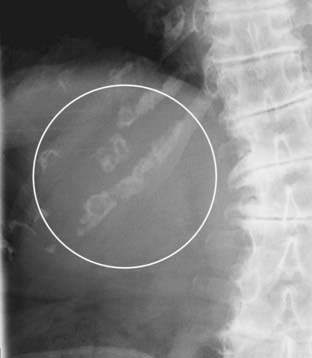

Figure 13-9 Normal small bowel valvulae.

Markings representing the valvulae typically do extend across the lumen of the small bowel to extend from one wall to the other. In addition, the valvulae are spaced much closer together than the haustra of the large bowel, even when the small bowel is dilated. The solid black arrows point to two valvulae that traverse the entire lumen in this enhanced close-up of dilated small bowel in this patient with a small bowel obstruction.